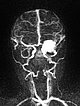

Dynamic contrast-enhanced MR angiography of the skull and cerebral vessels. In the very early arterial phase (A) no yet enhancement of the lesion in the left eye.

Dynamic contrast-enhanced MR-angiography in the arterial phase, 5 seconds later, depicts early and intense enhancement of the tumor in the left eye.